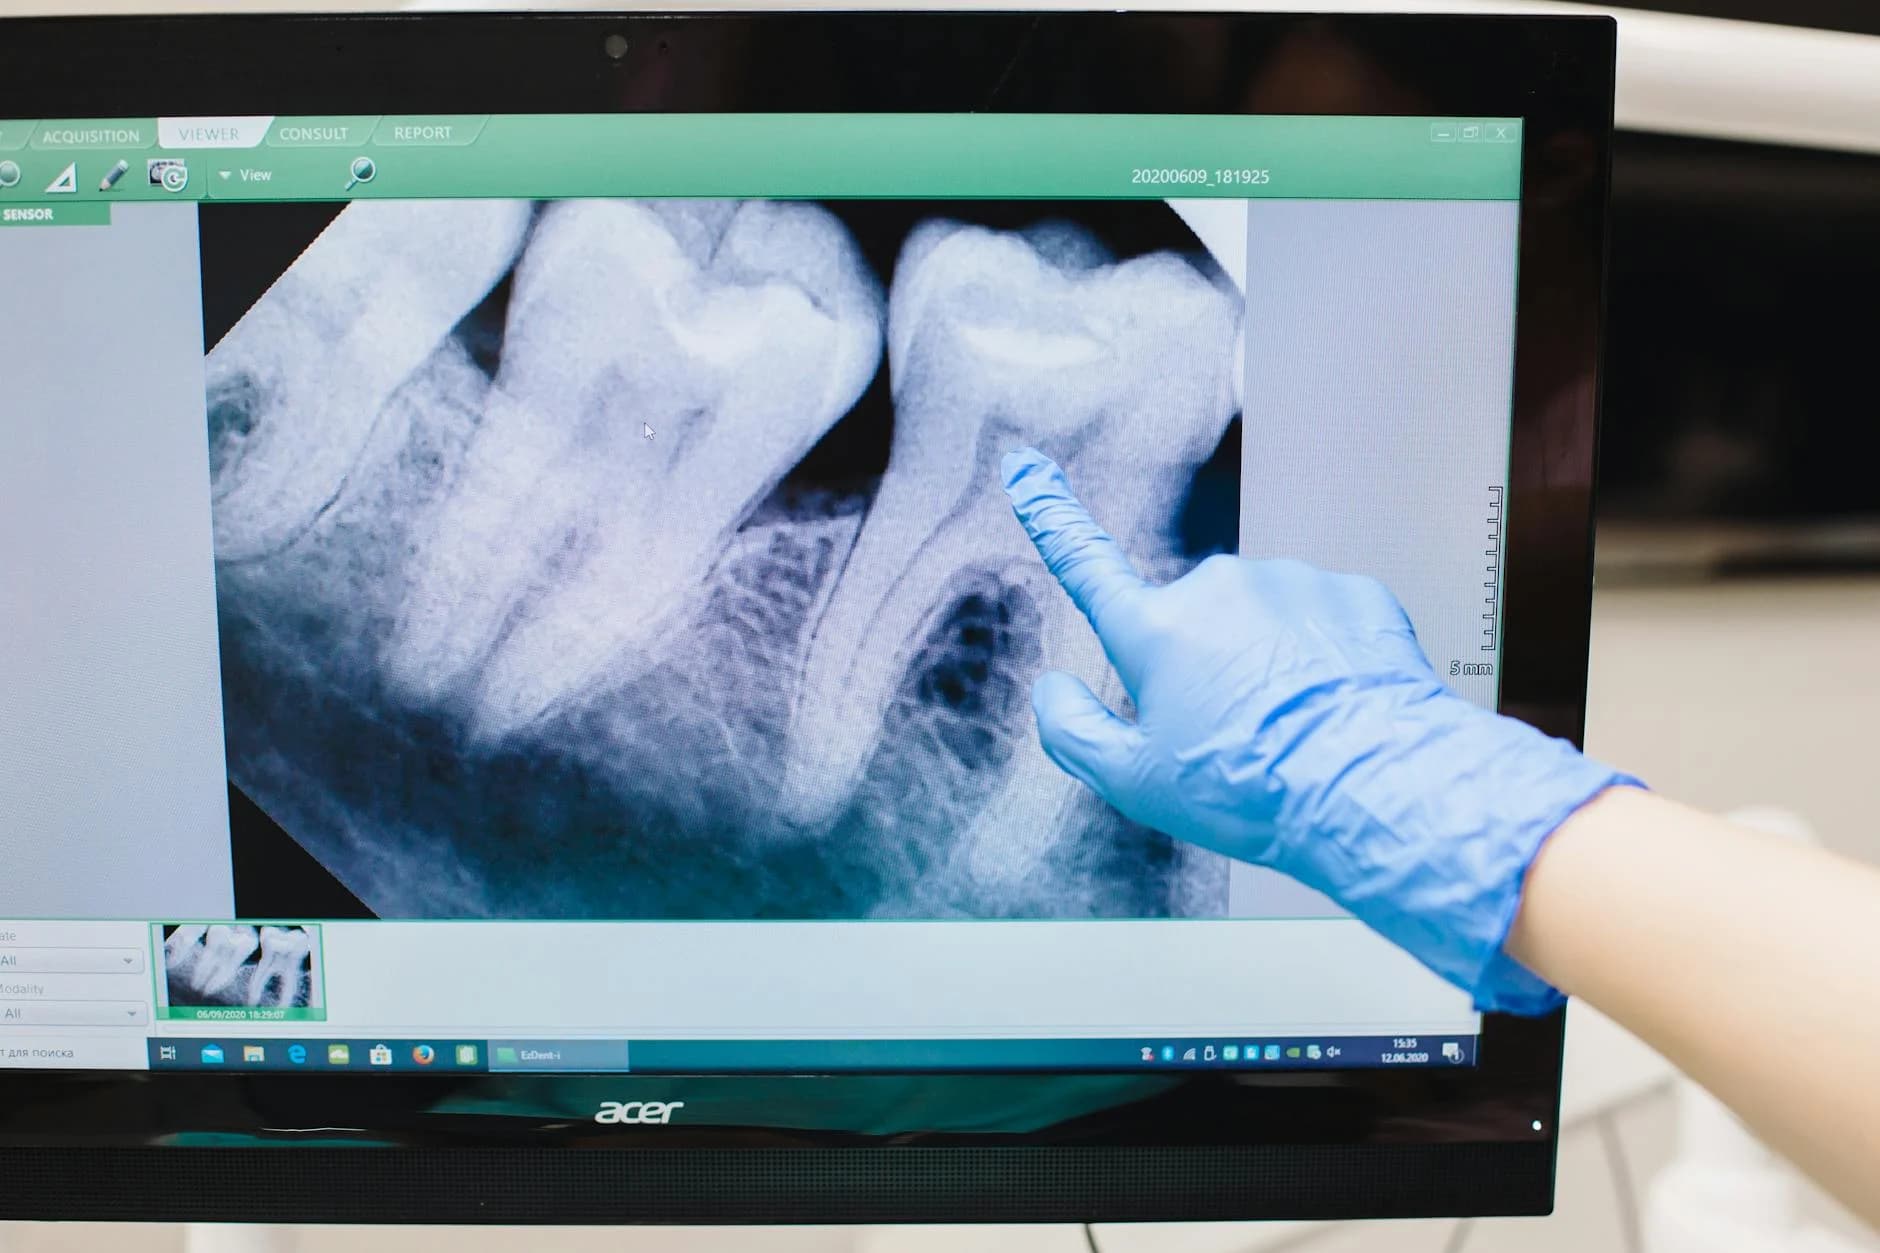

- Utilstrækkelig undersøgelse: Der blev ikke foretaget en grundig nok klinisk og radiologisk vurdering. Da man var i tvivl om tandens placering, burde den kliniske undersøgelse have været suppleret med nye røntgenbilleder.

- Overser tidligere journaldata: Journalen og røntgenbilleder fra den 19. juni 2024 viste, at mælketanden +05 allerede var fjernet tidligere. Desuden havde den blivende tand en atypisk form, hvilket burde have skærpet opmærksomheden hos behandleren.